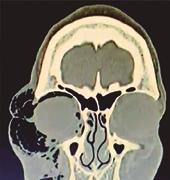

Estudiado el caso en ateneo, se plantea la posibilidad de la existencia de un remanente intraocular por lo que se realiza una tomografía axial computada (TAC) donde se evidencia cuerpo extraño intraocular (CEIO) de 10x2x1 mm. Por ecografía ocular se define ubicación exacta: retroiridiana en hora 7 en cuerpo ciliar.

Imagen corneal computarizada de zona de transición injerto-receptor